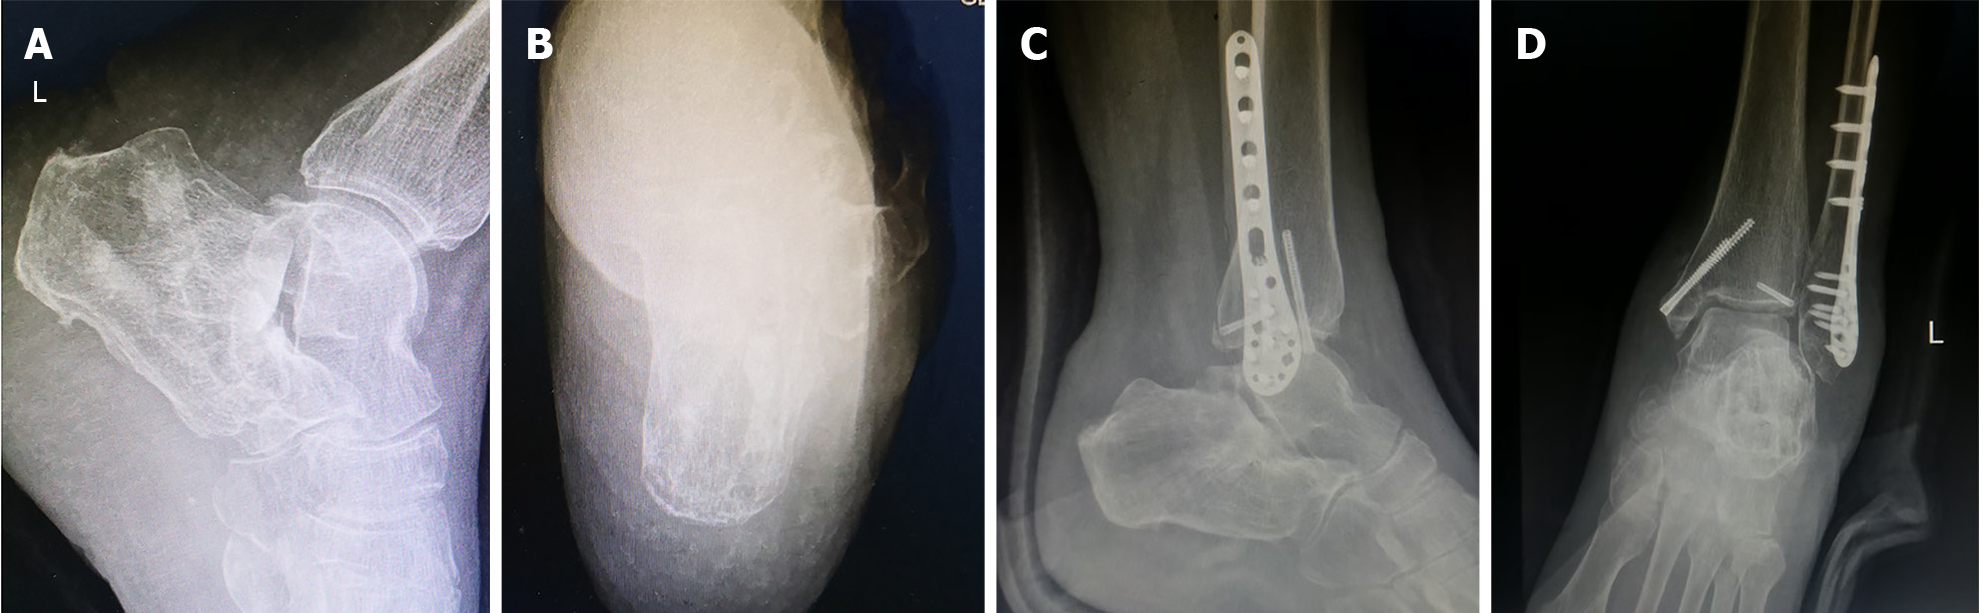

Figure 1 Radiographs revealed the patient’s comminuted calcaneal fracture.

A and B: Anteroposterior (A) and lateral (B) views of the ankle; C: Axial view of the calcaneus; D: Böhler angle was 0°.